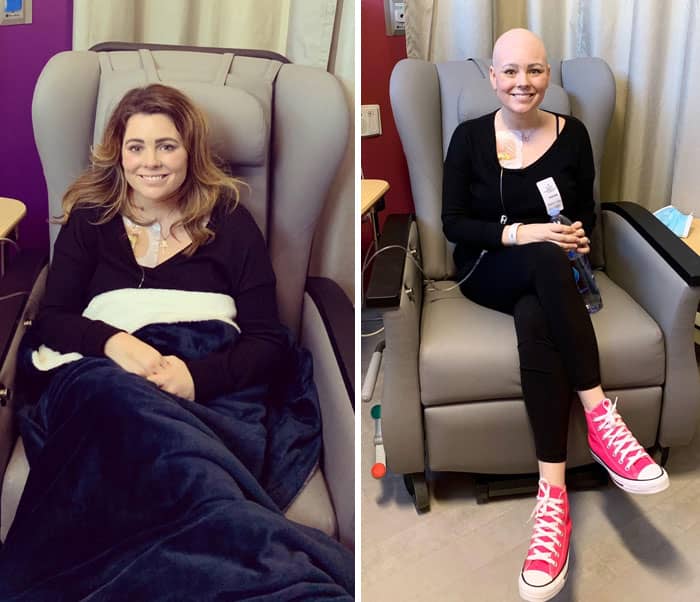

#3 First Day Of Chemo vs. Last